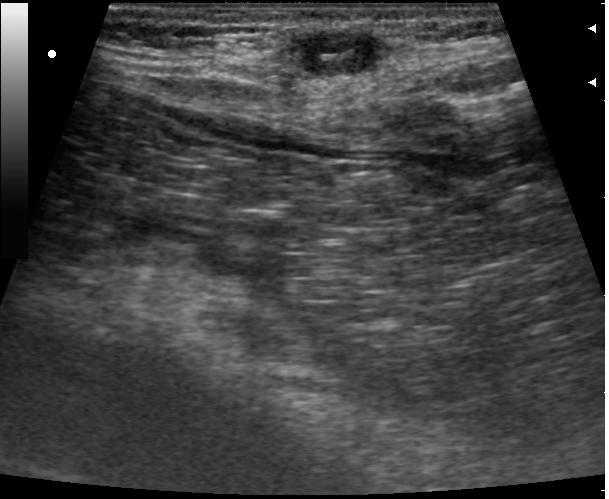

передняя брюшная стенка

просто прикольно выглядит, на коже изменений практически никаких. пациент сам по-себе с приколами (после операции б-нь Гиршпрунга, оперировали не у нас) показать?

Здесь в перспективе возможен лигатурный свищ.

Ну, как я и думал, более полугода.

Лигатура с изменениями окружающих тканей (стрелка)